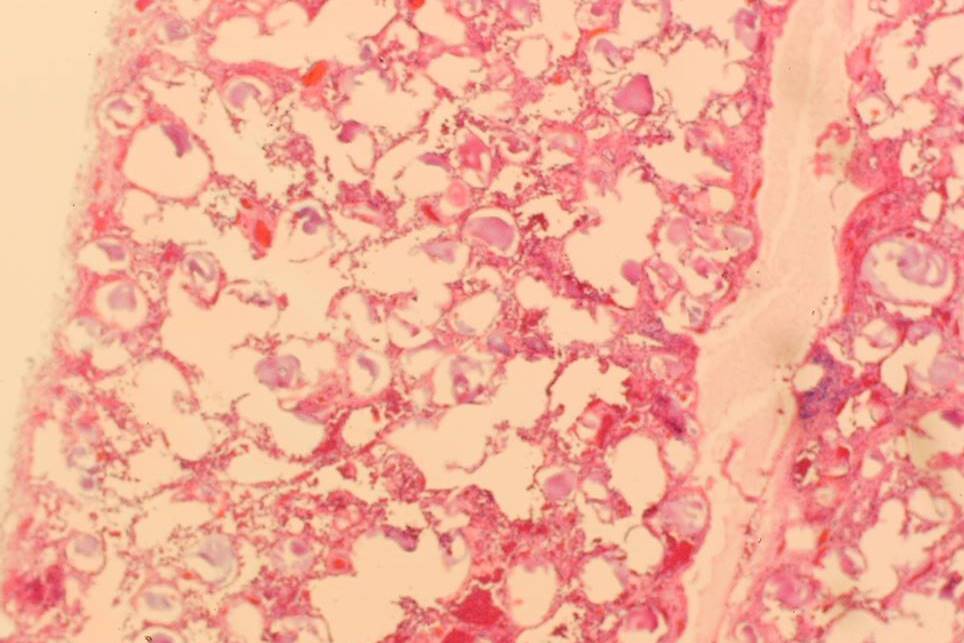

Bronchoscopy showed no endobronchial abnormalities. The total cell count in the bronchoalveolar lavage fluid was 60/mm3 with 86% alveolar macrophages, 12% lymphocytes and 1.0% eosinophils. CD4/CD8 ratio was 2.8. Microbiological exam of bronchial aspirate revealed no bacteria, mycobacteria or fungi. Neither transbronchial nor transthoracic lung biopsy were diagnostic. A surgical pulmonary biopsy was performed and revealed aggregated non-necrotizing granulomas with occasional multinucleated giant cells (figure 3). These histopathological features were compatible with sarcoidosis. Galium scan showed mild uptake in the hilar and ocular regions. These findings were of uncertain clinical value.

Figure 3 Lung biopsy specimen showing aggregated non-necrotizing granulomas with occasional multinucleated giant cells